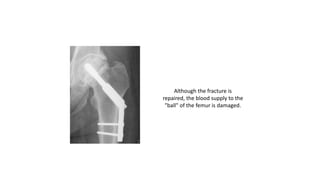

Although the fracture is

repaired, the blood supply to the

"ball" of the femur is damaged.